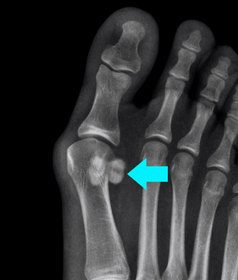

Sesamoid Fracture

What is a Sesamoid Fracture?

A sesamoid fracture is a break in the sesamoid bone. Sesamoids are two small, pea-shaped bones located in the ball beneath the big toe joint at the bottom of the foot. Sesamoid bones are connected to muscles and other bones by tendons that envelop these bones. Sesamoids help the big toe move normally and absorb the weight placed on the ball. A podiatrist is a doctor specializing in the treatment of foot problems including sesamoid fractures.

One or both of the sesamoid bones lie near the first metatarsophalangeal (MTP) joint. Untreated sesamoid fractures can cause cartilage problems and arthritis of the MTP joint.

Your doctor will assess your symptoms and take a medical history. Physical examination of the foot will be performed by moving your big toe. Your walking pattern will also be analyzed. Imaging studies such as X-ray, MRI or CT-scan will be ordered to confirm the diagnosis.